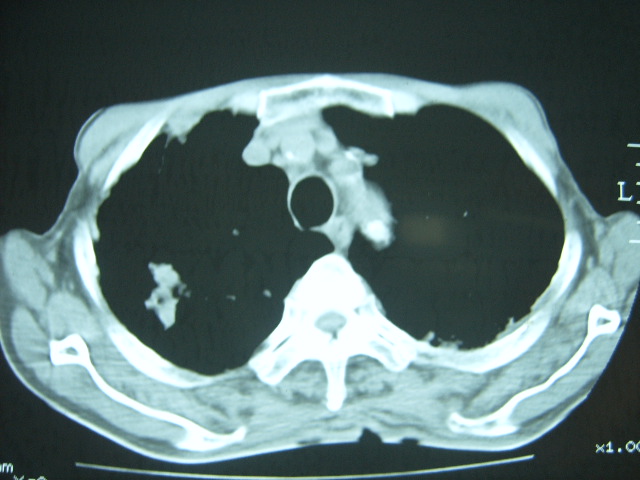

男74岁,咳嗽,寒战,低烧。有糖尿病史。

考虑:1、左下肺脓肿;

2、双肺结核。

考虑:糖尿病合并:1、左下肺炎继发肺脓肿;